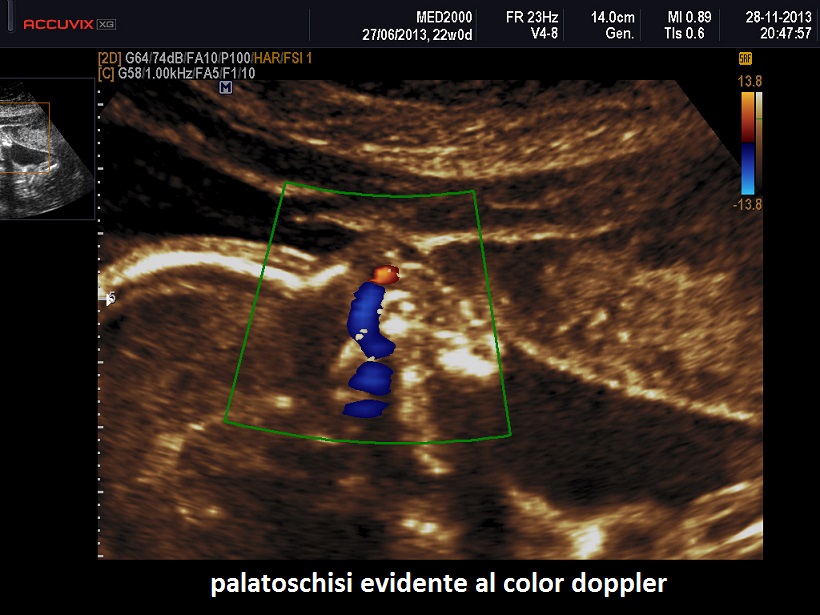

• palatoschisi